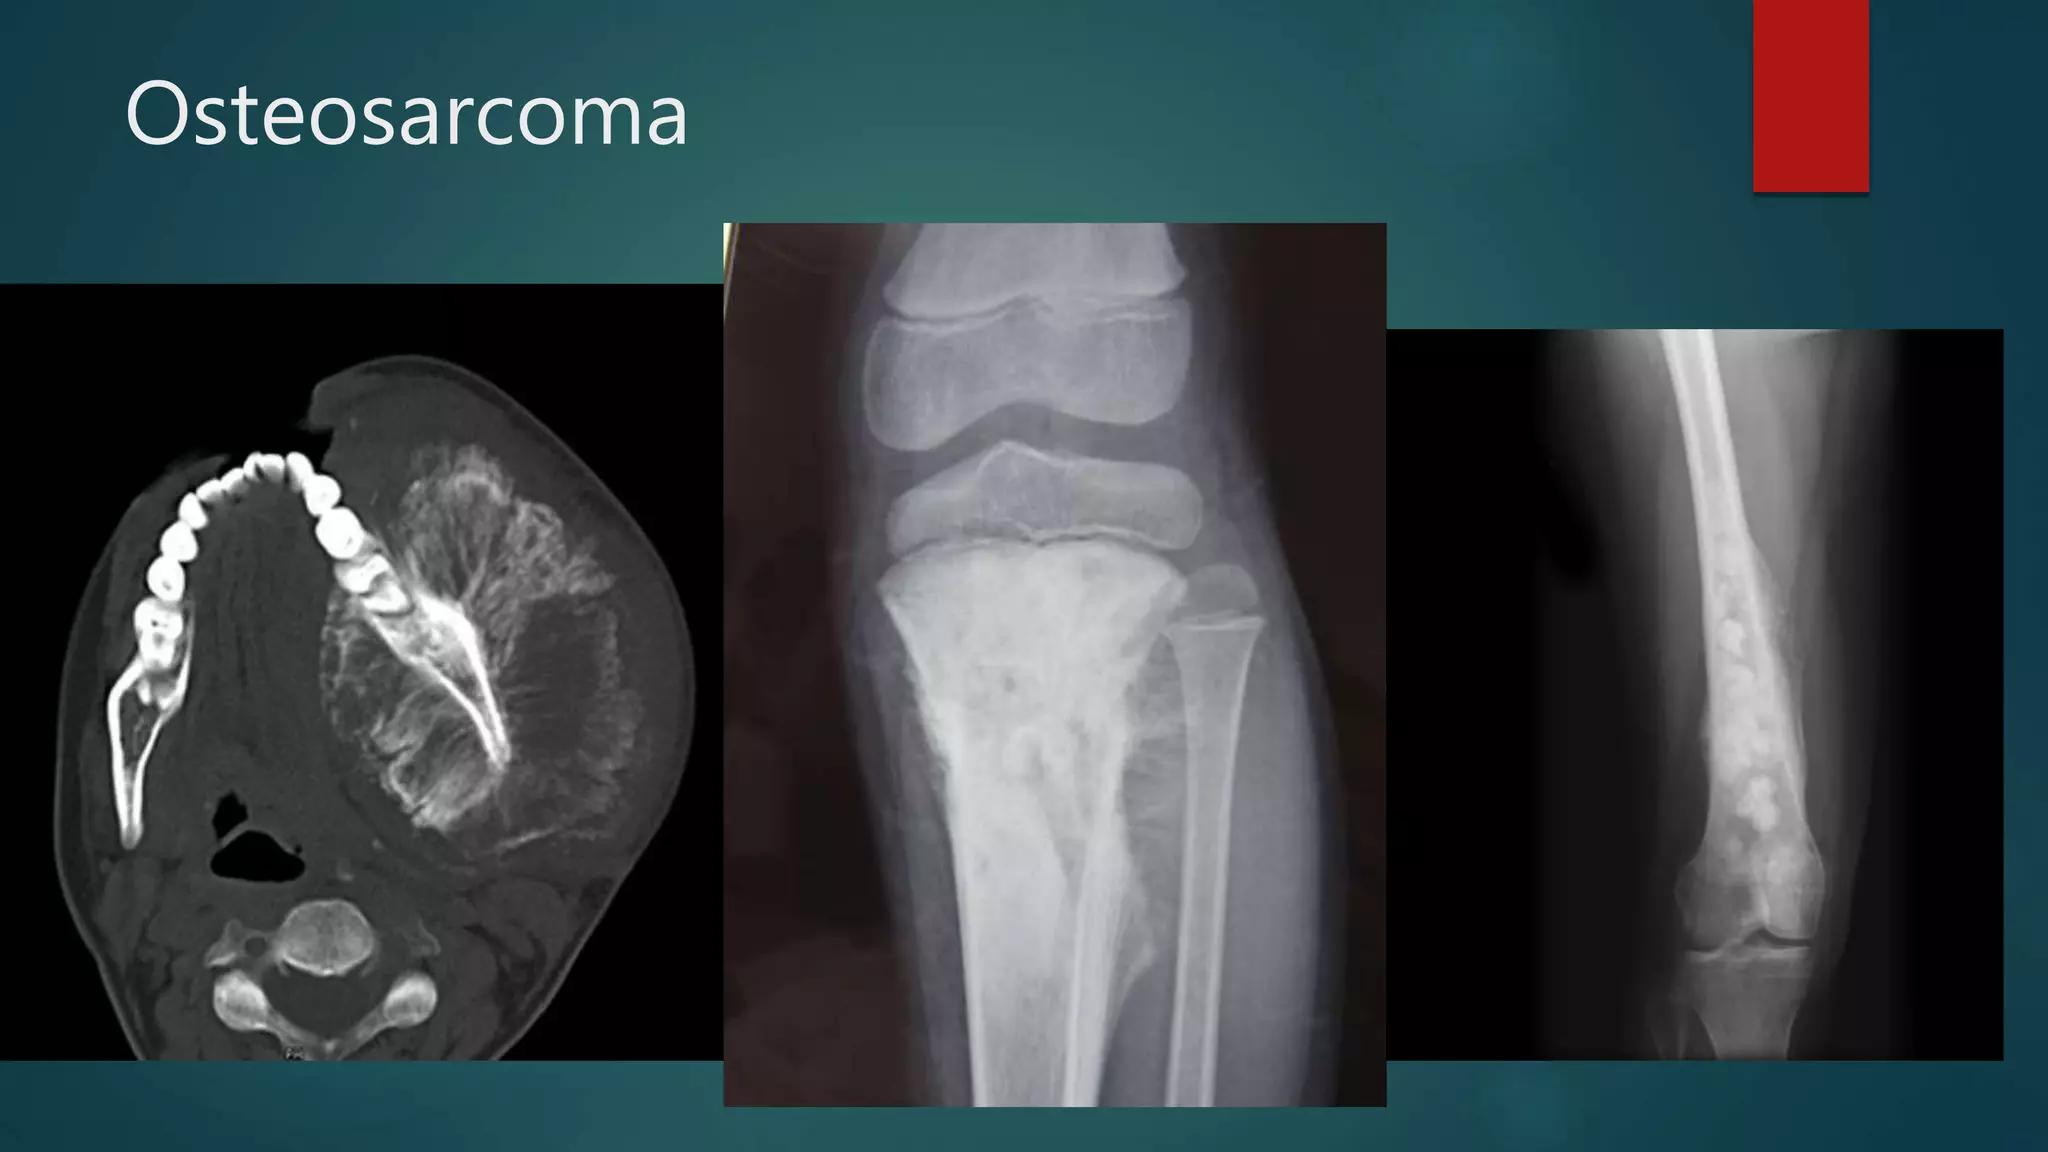

Osteosarcoma

Osteosarcoma Calcified mets in lungs

• #99 he distal half of the femur is occupied and expanded with a heterogeneous mass with areas of bone formation. Posterior the periosteum is elevated (Codman's triangle).